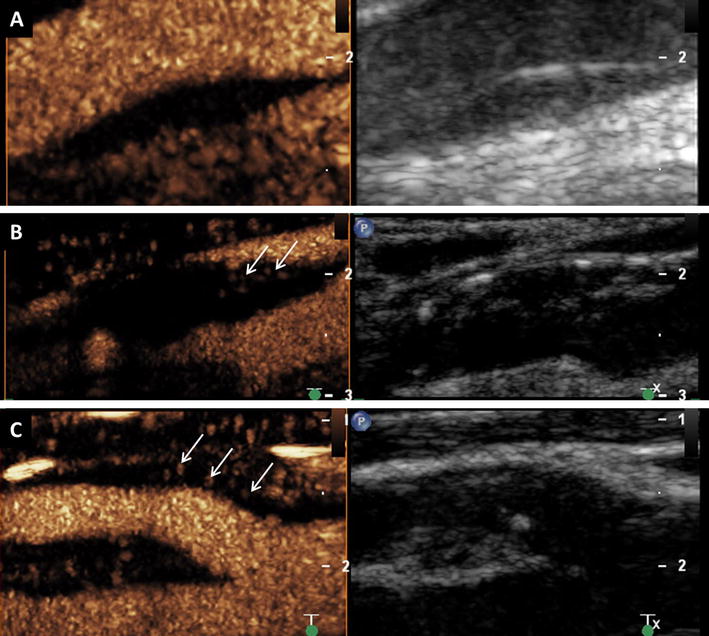

Visual based grading of intraplaque neovascularization on CEUS imaging. a No enhancement: Small plaque on the fare wall of the internal carotid artery on B-mode ultrasound (right side) without intraplaque neovascularization on CEUS imaging (left side). b Moderate enhancement: Mixed hypo- and hyperechoic plaques at the carotid bulb on B-mode ultrasound (right side) and CEUS imaging (left side) with moderate intraplaque neovascularization on the plaque shoulder (arrows). c Extensive enhancement: Hypoechoic plaque at the origin of the internal carotid artery on B-mode ultrasound (right side) and CEUS imaging (left side) with extensive intraplaque neovascularization including the plaque core (arrows)